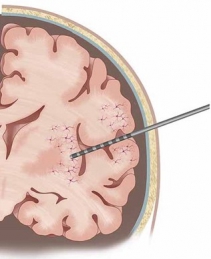

Our research leverages on the rare opportunity of measuring brain activity intracranially in patients affected by pharmaco-resistant epilepsy. In pharmaco-resistant epilepsy patients, neurologists use intracranial electroencephalography (iEEG) to delineate the epileptogenic focus, when non-invasive scalp EEG and other techniques have been insufficient to localize it. iEEG is recorded with intracranial electrodes and it has higher spatial resolution and higher signal-to-noise ratio than scalp EEG.

iEEG is generally more used in mesial temporal lobe epilepsy. Therefore, the clinical intracranial macroelectrodes often record electrophysiology signals from the hippocampus, the entorhinal cortex and the amygdala, which are very important for cognitive processes such as memory. However, other areas, such as the frontal cortex, are also not uncommon implantation targets.

| image credits [1] | image credits [2] |

1. © Grande et al. 2020. The image is a cropped version of the original. Reproduced according to the terms of Creative Commons Attribution License. Grande, Krista M., Sarah K. Z. Ihnen, and Ravindra Arya. 2020. “Electrical Stimulation Mapping of Brain Function: A Comparison of Subdural Electrodes and Stereo-EEG.” Frontiers in Human Neuroscience 14 (December). https://doi.org/10.3389/fnhum.2020.611291.

2. © Greene et al., 2021. Reproduced according to the terms of Creative Commons Attribution License. Greene, Patrick, Adam Li, Jorge González-Martínez, and Sridevi V. Sarma. 2021. “Classification of Stereo-EEG Contacts in White Matter vs. Gray Matter Using Recorded Activity.” Frontiers in Neurology 11 (January). https://doi.org/10.3389/fneur.2020.605696.